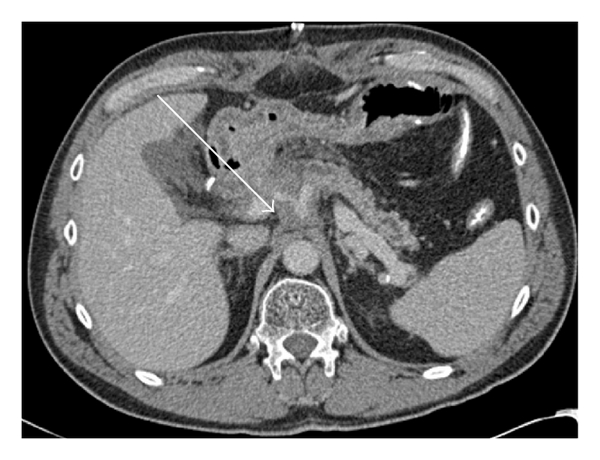

As Figures 1–5 demonstrate, the immediate postablation bed and zone are invariably larger than the original ablated tumor. We remain descriptive because the entire bed was extremely difficult to measure owing to the amorphous, irregular nature of the ablation. Moreover, the ablated tissue is not within an encapsulated organ; therefore, the ablation zone does not have defined borders as seen after, for instance, liver ablation. Four patients that showed continued stable disease are highlighted in Figures 1 through 4. An amorphous, hypoattenuating region with irregular shape persisted in subsequent CT scans in all patients with “stable disease.” Moreover, the ablation zone was typically smaller (due to decreased edema, hyperemia, and granulation tissue) than the immediate postablation bed in the following months and remained stable provided there was no recurrence. Imaging findings demonstrating recurrence are shown in Figure 5. Along with persistent irregular shape the ablation zone showed increased tumor bulk and extension as well as new mass effect (new narrowing of a blood vessel). Enhancement of the ablative bed was variable and often showed increased enhancement in the three-month and longer follow-up images. This was felt to be related to development of granulation tissue and fibrosis.

In our study, we found that the postablation bed is larger in volume than the initial mass. This is expected because it contains the tumor and the ablative margin. The postablation bed and zone appear irregular, amorphous, and hazy without margins or true boundaries. The ablation zone may decrease in size from the initial post-op bed to the initial surveillance study as the surrounding edema/fluid and inflammation resolve revealing the true ablation zone; however, as mentioned above, since there have been reports of an ongoing apoptotic process that persists up to 6–8 weeks after ablation, it will not be unusual to see some increase in volume in surveillance [19, 20]. Therefore, size is considered secondary in the CT evaluation for this reason and because the postablative bed/zone has poorly defined margins, making objective imaging assessment (size, attenuation) cumbersome. This may undoubtedly affect the accuracy and reproducibility of the measurement. Nonetheless, any increase in volume after stabilization of the postablation zone is considered worrisome for recurrence (Figure 5).

Other clues that may suggest recurrence are any new encasement or narrowing of adjacent vessels or any subjective extension of soft tissue outside the boundaries of the previously established baseline ablation zone. However, in patients that have undergone prior radiation therapy or undergo post-IRE radiation therapy, persistent isolated narrowing (without other worrisome findings) is not always recurrence and must be followed with serial imaging, clinical evaluation, and CA19-9 serum tumor markers. Vessels within and adjacent to the ablation bed may show narrowing immediately after the procedure, but this should resolve or at least remain stable in subsequent studies. Often, if narrowing of a vessel is seen with the index tumor it will often persist after ablation. For equivocal cases, PET/CT may play a role in differentiating postablative changes from recurrence [25].